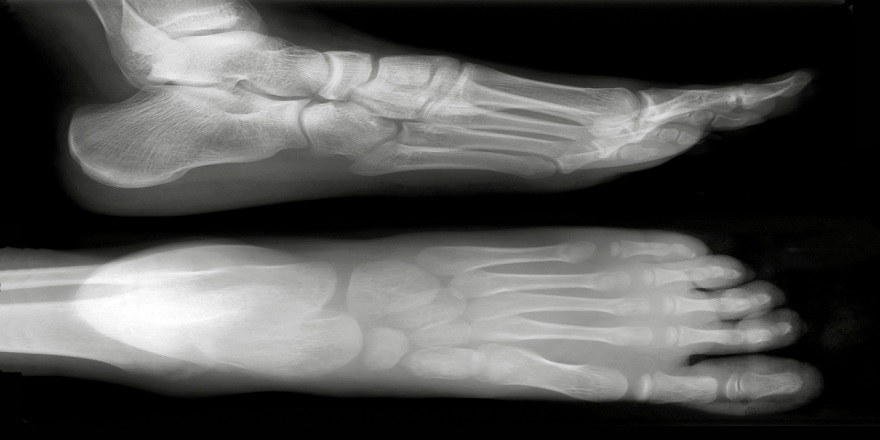

Kırığın üç belirtisi ağrı, şişme ve şekil bozukluğudur. Ayrıca olay anında kırılma sesi duymak da mümkündür.

Ayak parmağındaki kırık ve çatlaklarda alçıya alma söz konusu olmasa da kırığın çapını belirlemek ve uzun vadede ağrı ve deformasyona engel olmak için doktora görünmek gerekir. Kırık kötü bir açıda oluşmuşsa daha karmaşık bir tedavi, hatta ameliyat gerekebilir.

Kırık ayak parmakları çoğu zaman yanındaki parmaklara yapışık şekilde tutulur ve sert bir kalıp takılabilir. İyileşme süreci 4-6 haftadır. Ancak ayak baş parmağındaki kırıklar daha ciddidir ve bazen baldıra kadar alçıya alınıp 2-3 hafta bekletmek gerekebilir. Ama bunların kırılma ihtimali diğer parmaklardan daha düşüktür.

Kırık ayak tarağında ise, yandaki kemikler doğallığından birbirini düz tuttuğu için alçıya gerek olmaz ve ayak dinlendirildiği takdirde çoğu zaman düz bir şekilde iyileşir. Ancak baş ve küçük parmağın altındaki kemiklerin desteği olmadığından bunlarda ameliyat gerekebilir.

Alçıya almak gerekmese bile ayak parmaklarındaki kırık ve çatlakları doktora göstermek gerekir. Sağlık görevlileri parmağa destek olacak şekilde sargı takabileceği gibi, koltuk değneğine ihtiyaç olup olmadığını da belirleyebilir.